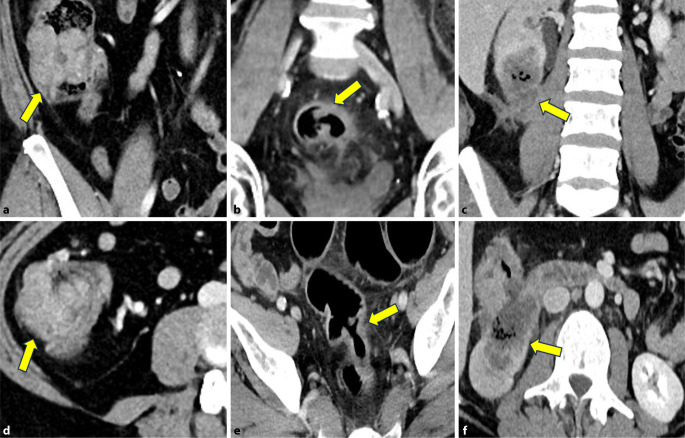

Background: Imaging, specifically magnetic resonance imaging (MRI), has long been the cornerstone for staging rectal cancer. In contrast, computed tomography (CT) is the standard for colon cancer staging. Primary staging is essential for individualized risk stratification and therapy planning.

Results: TNM staging includes local tumor extension as well as the presence of lymph node and distant metastases. For local tumor extension, MRI is very well suited for rectal cancer. In colon cancer, CT shows significant limitations regarding the sensitivity of differentiating individual stages. Lymph node metastases can pose a major challenge for both MRI and CT, which has led to the definition of several malignancy criteria. The detection of distant metastases remains primarily within the domain of CT, except for liver metastases.

Conclusions: Depending on tumor location, either MRI or CT is recommended for primary staging of colorectal cancer, and a combination of both modalities may also be appropriate. Accurate assessment of the primary tumor, lymph nodes, and organs using imaging is an essential component of the therapeutic approach to colorectal cancer.